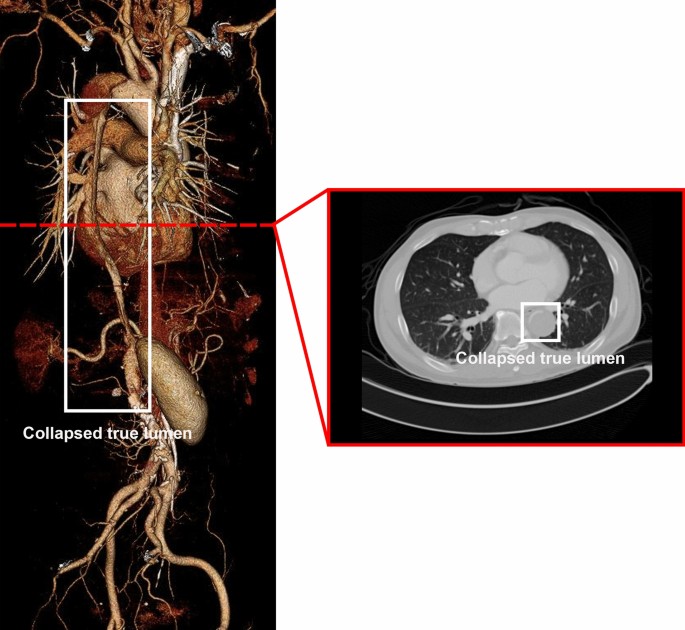

In AD, malperfusion is mostly caused by the collapse of the true lumen owing to the motion of the intimal flap, which obstructs branch vessels and results in end-organ ischemia (Fig. 1)5,10. Malperfusion can affect almost all major vascular beds, including the carotid, visceral, spinal, renal, and lower extremities, with varying frequencies and severity5,10,11,12. The malperfusion patterns depend on the region of the tear and dissection size. In the case of severe malperfusion, the affected organ may be injured by ischemia, which can significantly affect patient prognosis11,12. Thoracic endovascular aortic repair is a well-established method for treating malperfusion that comprises covering the primary entry tear, opening the true lumen, and thereafter relining the aorta to handle rupture. In addition, less invasive thoracic stenting has been used as an alternative to open repair, and end-organ malperfusion has been prevented by restoring visceral flow using endovascular fenestration4.

3D volume rendering and axial view of computed tomography in an AD patient with lower extremities malperfusion due to true lumen collapse. The image was reconstructed using TeraRecon (https://www.terarecon.com).